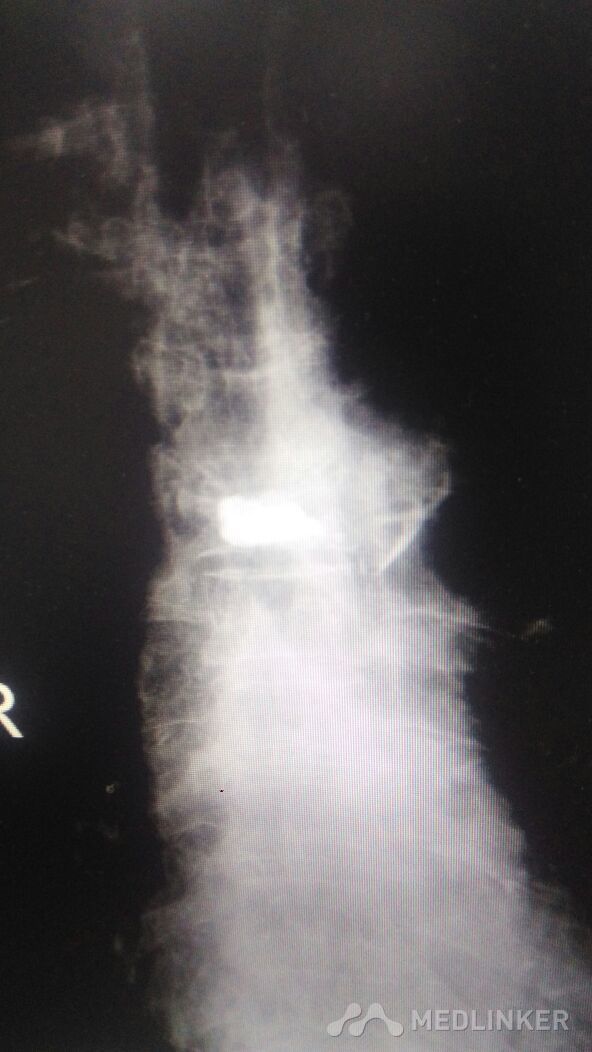

外科活动+胸椎体成形术。术后到术前很成形功。